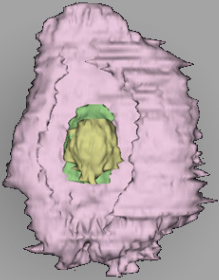

0 μm

Carnegie Embryo #8020 | Location: 06-04-07

Keywords: cytotrophoblast, edematous endometrial stroma (decidua), edge of blastocystic cavity (blastocoele), endometrial epithelium, endometrial gland, solid syncytiotrophoblast, uterine cavity

Source: The Virtual Human Embryo.